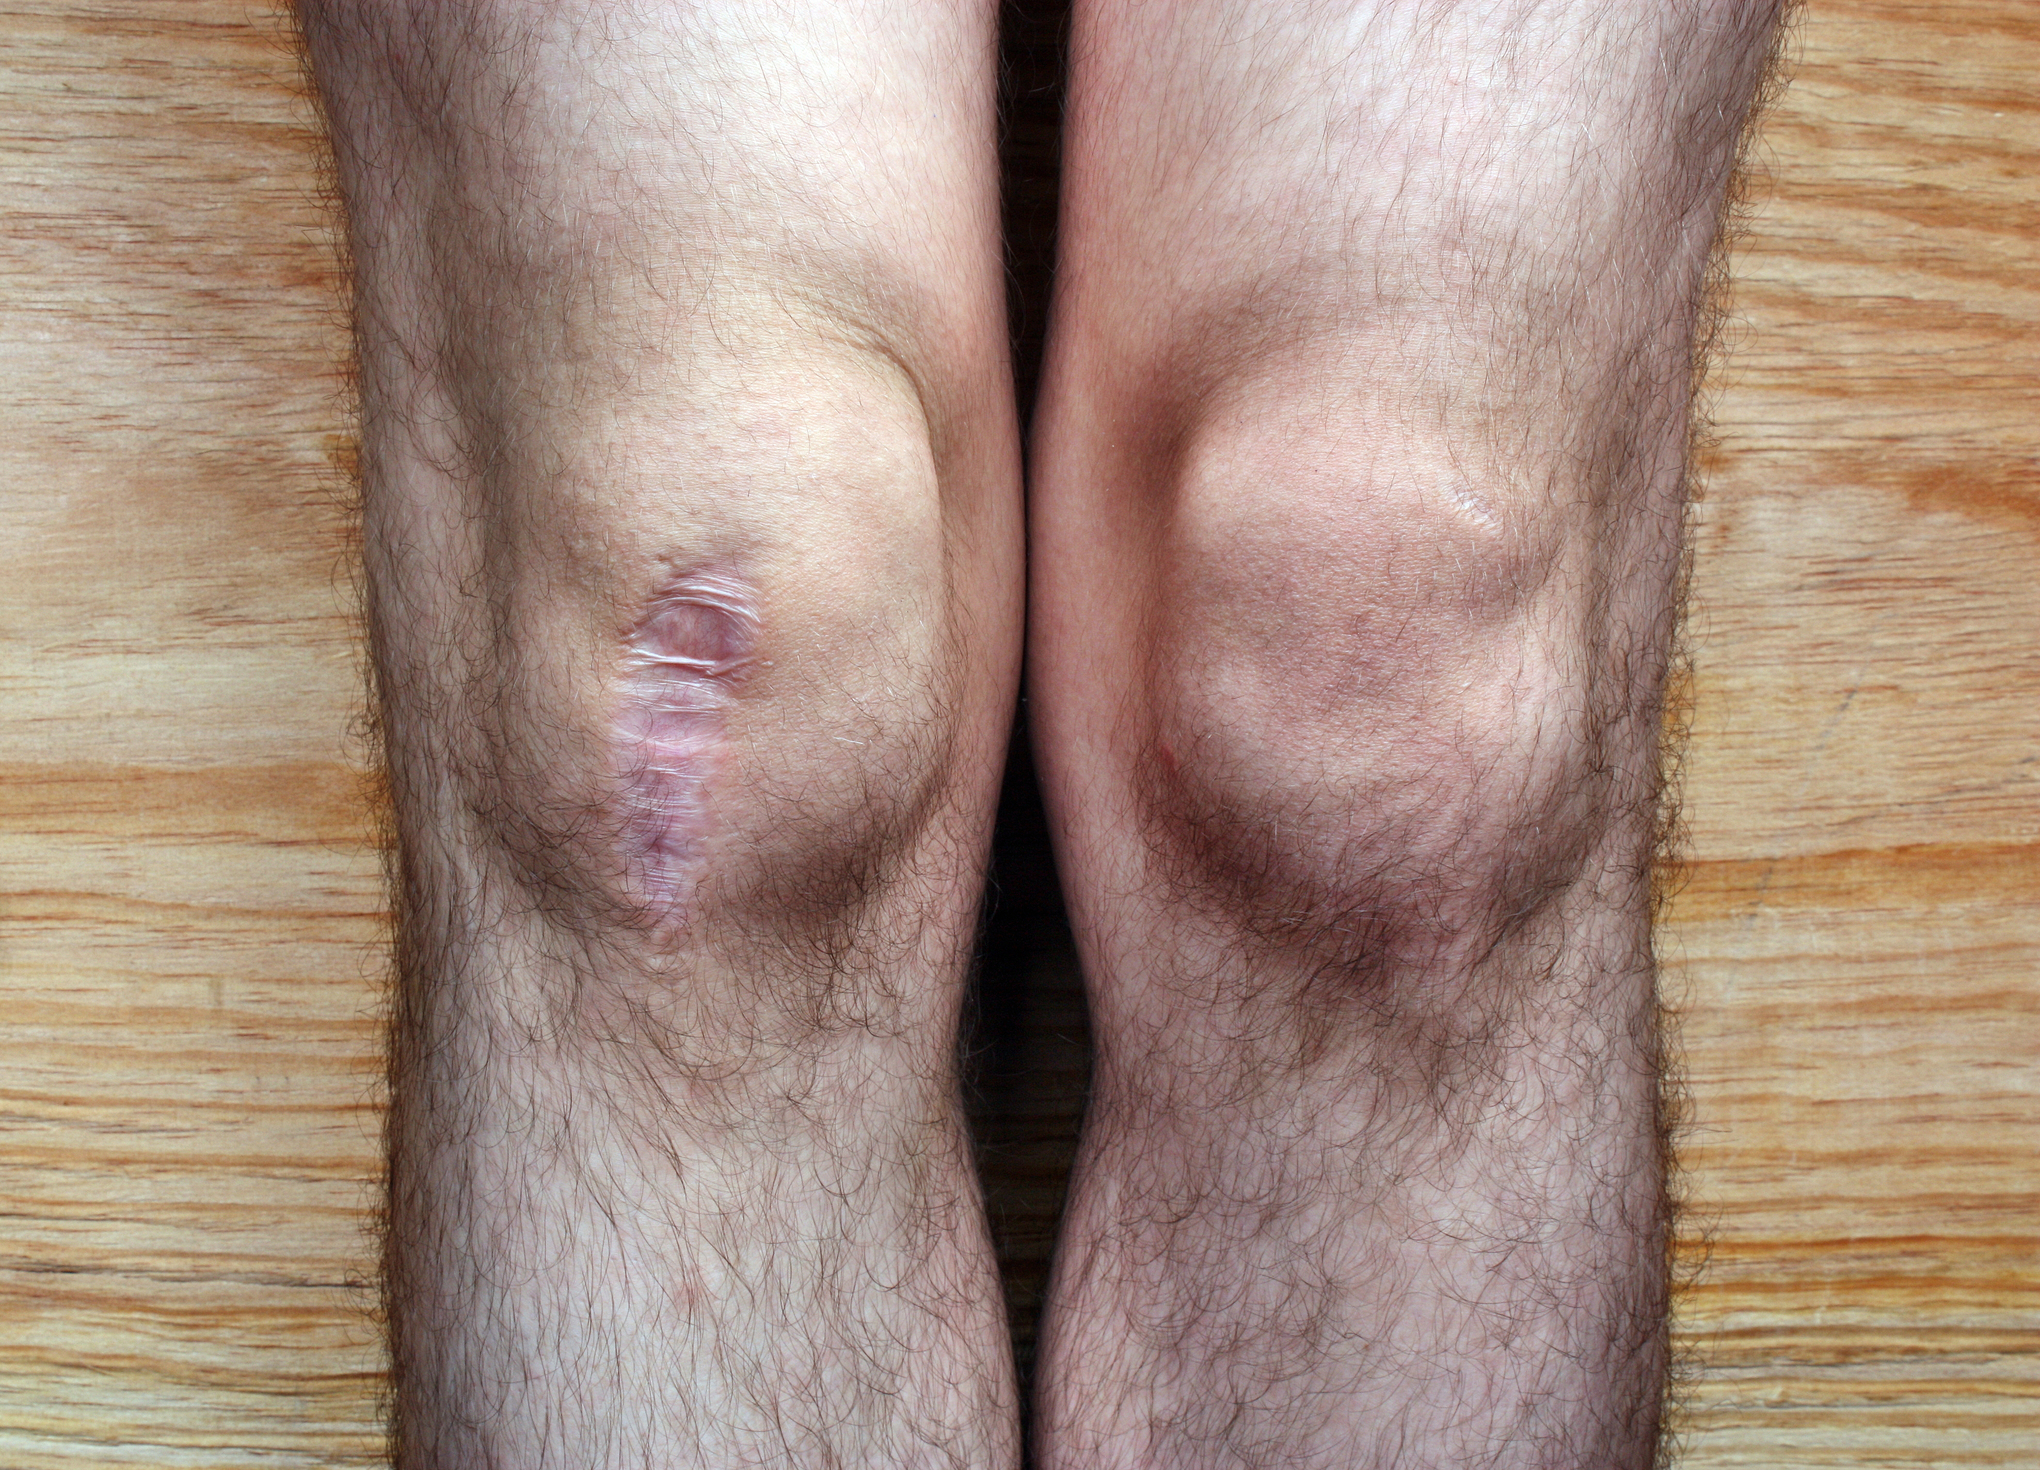

2. Bone-On-Bone Arthritis

A doctor will require x-rays to determine if the arthritis has progressed to the bone-on-bone stage. At this point, it is worth considering a knee replacement. For those with arthritis which shows only a deterioration of cartilage, it is probably not the best option. There are other treatment methods, and the arthroscopy may not result in a satisfactory replacement. When the bones are rubbing against each other, it causes extreme pain and damage.